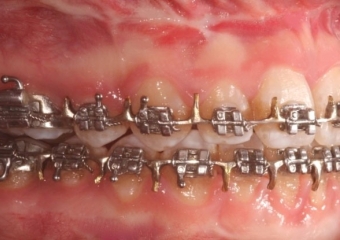

Mordida após a cirurgia